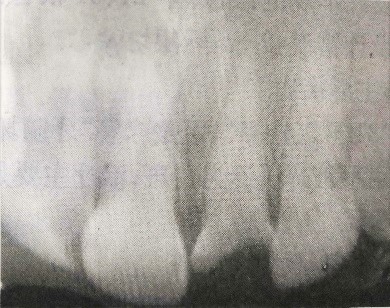

檢查:21牙冠缺損,黑褐色,根管口暴露,覆蓋污穢物,探診(-),冷測(-),叩診(+)。左上1唇側(cè)牙齦根尖部有白色瘺管出現(xiàn)。X線片檢查提示:21根尖區(qū)低密度影。全口牙齦紅腫,探診后出血,且下頜后牙區(qū)有附著喪失。相關(guān)情況請見下圖: